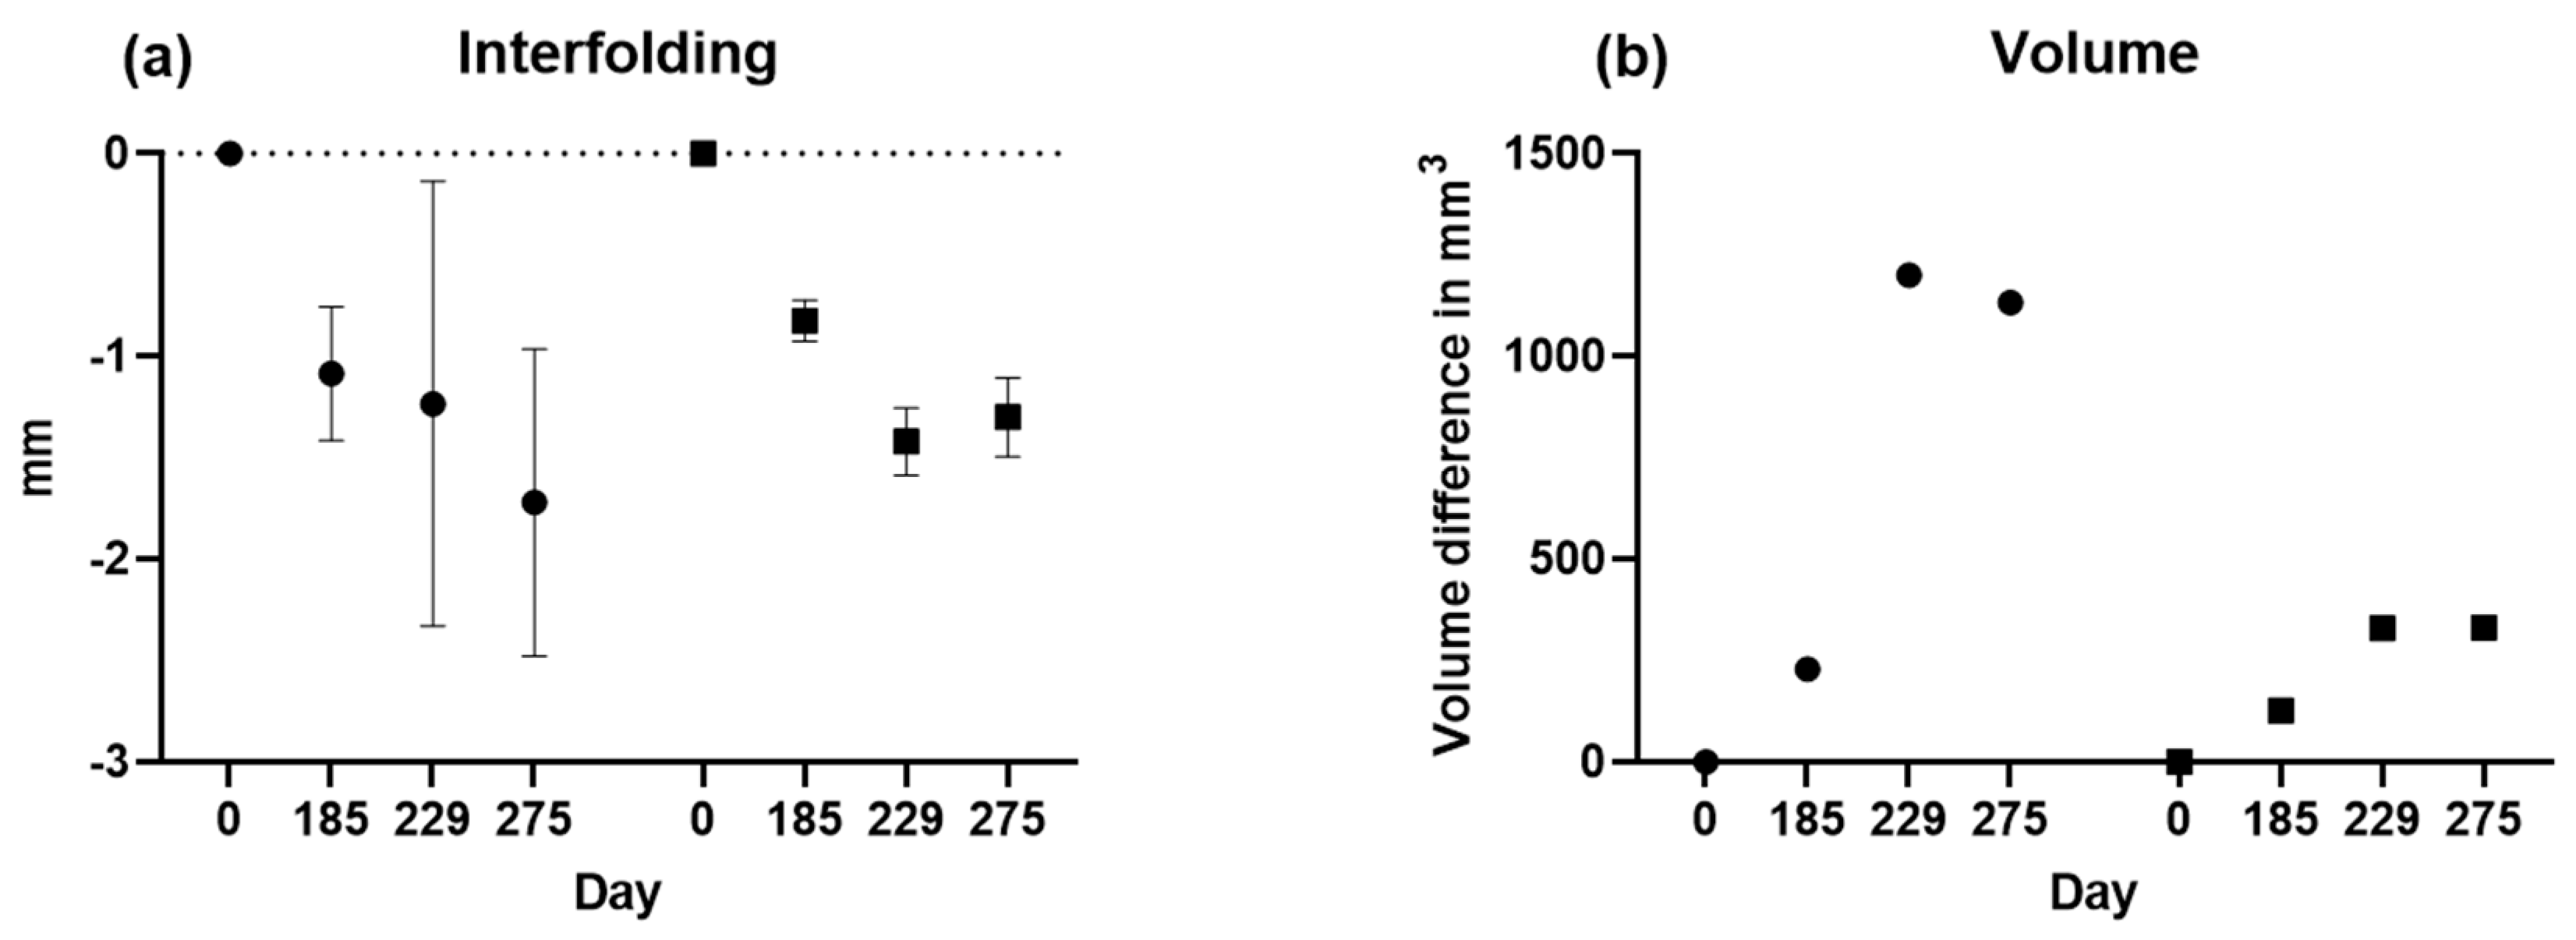

3.4. Three-Dimensional (3D) Measurements of Biparietal Thinning

3.5. Comparisons of Changes in Bone Loss over Time